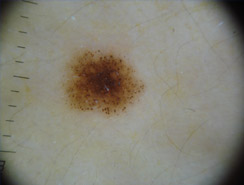

Dermatoscopia

Lo studio e la diagnosi delle neoformazioni cutanee attraverso strumenti specifici indicati per un'analisi delle caratteristiche strutturali superficiali e profonde delle varie neoformazioni cutanee: dermatoscopia, dermalite a luci fotocromatiche, mappatura nevica con videodermatoscopia digitale.

Al fine di una corretta diagnosi dei nevi, e dunque di un'efficace prevenzione da forme tumorali, è indispensabile visionare in profondità i caratteri di ogni formazione nevica. Ciò è reso possibile dall'utilizzo del dermatoscopio e dalla concomitante mappatura nevica, con l' eventuale rimozione chirurgica o laser di: